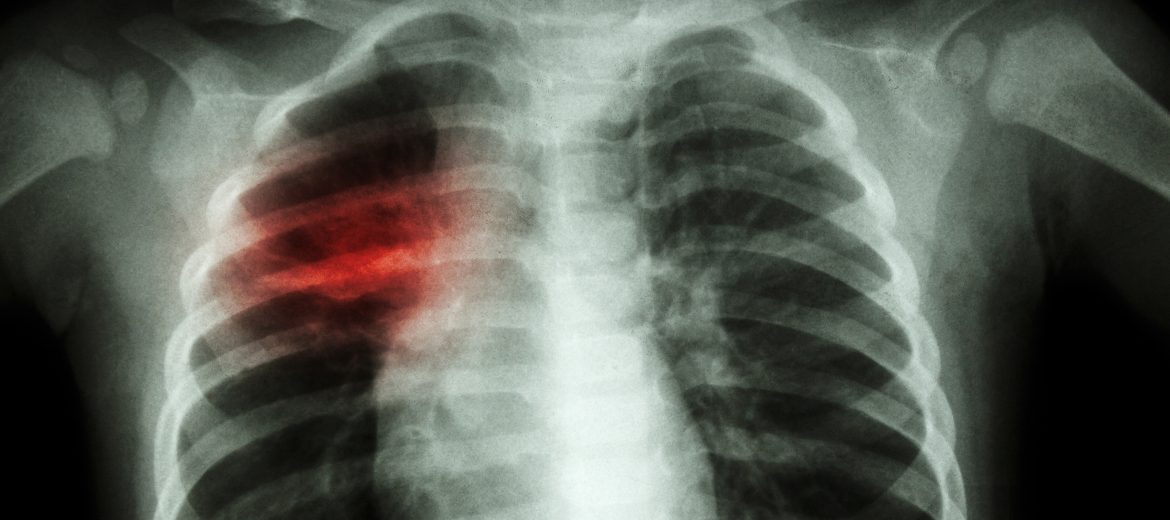

Chest X-ray of child showing patchy infiltration of tuberculosis at right middle lung